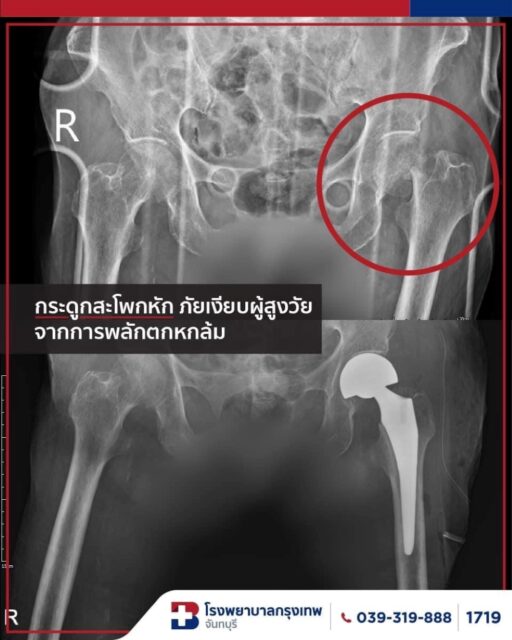

กระดูกสะโพกหักในผู้สูงอายุ